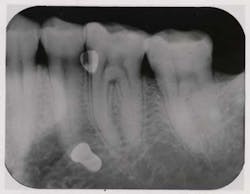

Fig. 1 — Pretreatment radiograph of the maxillary left second premolar. There is an advanced osseous lesion at the distal and suggestion of a developing periapical lesion.

By Paul S. Rosen, DMD, MSThere is a growing belief in dental practice today that if a tooth has advanced periodontal disease, it should be replaced with a dental implant rather than attempt to save it. Certainly, dental implants have been chronicled for their high level of success.1 But what if the loss of that tooth would lead to extensive restorative dentistry or the need for sophisticated procedures such as sinus elevation with concurrent bone grafting? Should the choice default to the implant or prosthetic option? Moreover, what about the patient’s desire to retain his or her own teeth?Regeneration is a treatment option for teeth with moderate to severe lesions that has demonstrated predictable success to achieve regeneration, new bone, cementum, and a functional periodontal ligament.2 Moreover, restoring these component tissues enhances the long-term survival of teeth.3 This case report documents one such instance where the loss of a premolar would have led to tremendous expenses for the patient for rehabilitation of this area.Case studyThis 63-year-old Caucasian female had been under routine periodontal maintenance care over the course of the last 10 years, having undergone comprehensive treatment that included surgery and rehabilitation with a fixed maxillary prosthesis. Her medical history was unremarkable except for osteopenia, for which calcium was taken. Maintenance visits were scheduled on a three-month interval and the patient was compliant with the prescribed care. Unfortunately, she experienced breakdown at the distal of the maxillary second premolar (Fig. 1) where clinical attachment loss and probing depths ranged up to 8 mm and mobility was 1+ degree. Furthermore, there was a separate but coincident periapical lesion (Fig. 2).